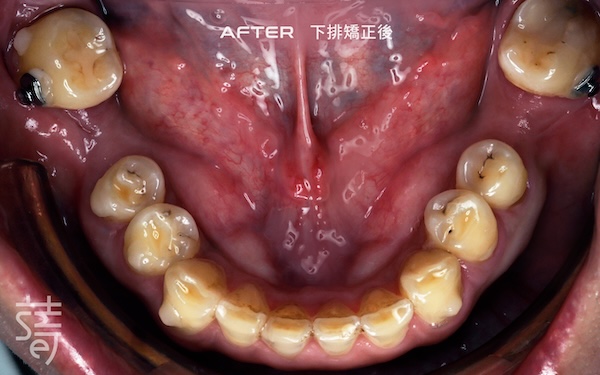

第一階段:隱適美矯正 Stage One: Invisalign Alignment

將牙齒重新排列整齊,調整上下咬合,把原本傾倒的第二大臼齒推回正確位置,為後續植牙和假牙重建打好基礎。

Teeth were realigned, the bite adjusted, and the previously tilted second molars repositioned, laying a solid foundation for implants and prosthetics.